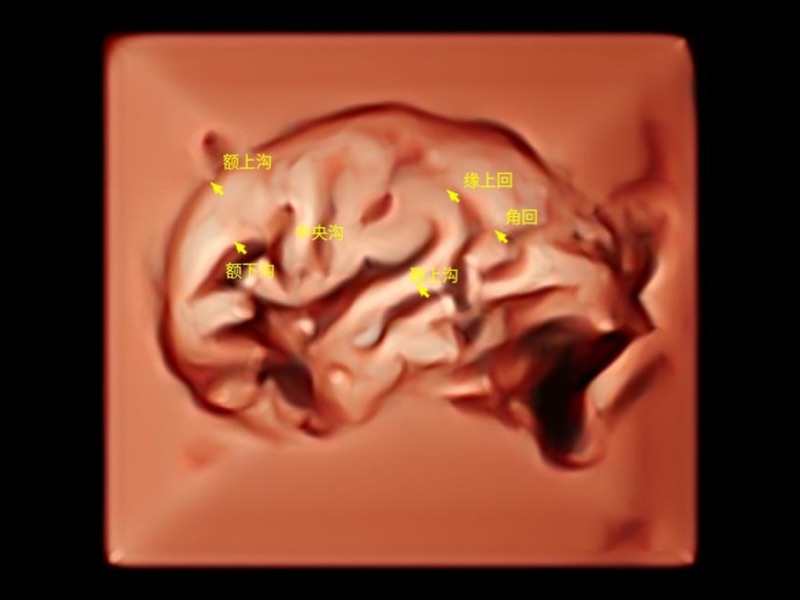

胎兒顱腦融合

時(shí)間空間相關(guān)成像